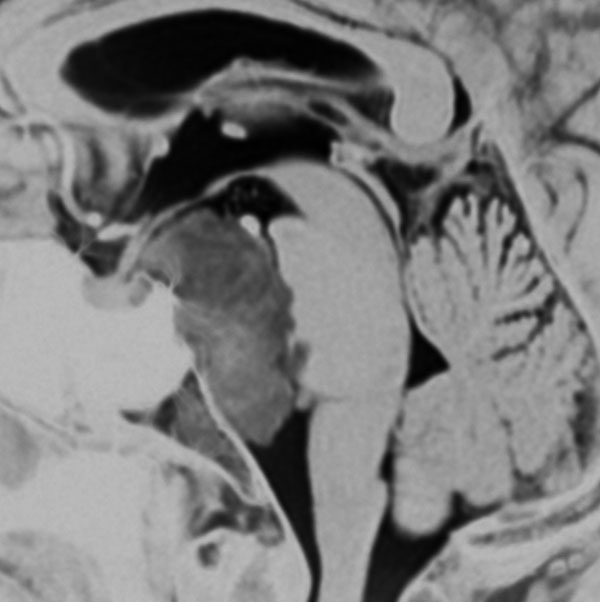

巨大なエコルドーシス・フィサリフォラ

T2強調画像とFLAIR像です。FLAIRでは髄液より高信号となります。のう胞様の膨らみを有します。脊索腫と異なり,expanding mass と表現されます。

CISSとガドリニウム増強T1強調画像です。ガドリニウム増強されません。

拡散強調画像ではわずかに高信号です。類表皮のう胞や類皮のう胞との鑑別が可能です。